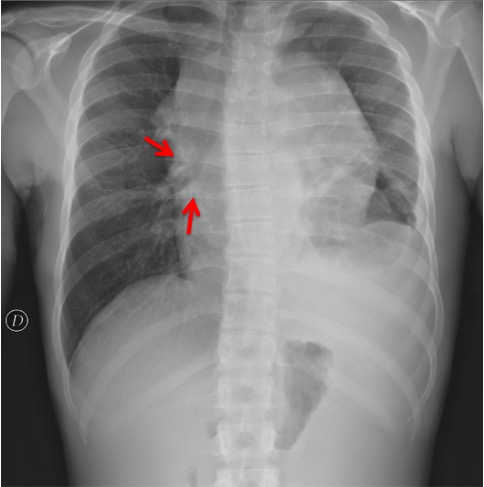

CASO: sospecha de neumonía.

Hallazgos:

- En un principio podríamos decir que existe un aumento de densidad retrocardiaco que podría ser compatible con condensación neumónica a dicho nivel, sin embargo estamos ante una placa poco inspirada, lo cual puede llevarnos a cometer errores diagnósticos.

- Se recomendó volver a realizar la radiografía, observar a continuación:

Ya no se observa el aumento de densidad retrocardiaco, la placa es normal.

INSPIRACIÓN: Una placa bien inspirada es aquella en la que se observar 6-7 arcos costales anteriores o 10-11 arcos costales posteriores. Lo contrario puede producir imágenes falsas de condensaciones o de seudocardiomegalia.